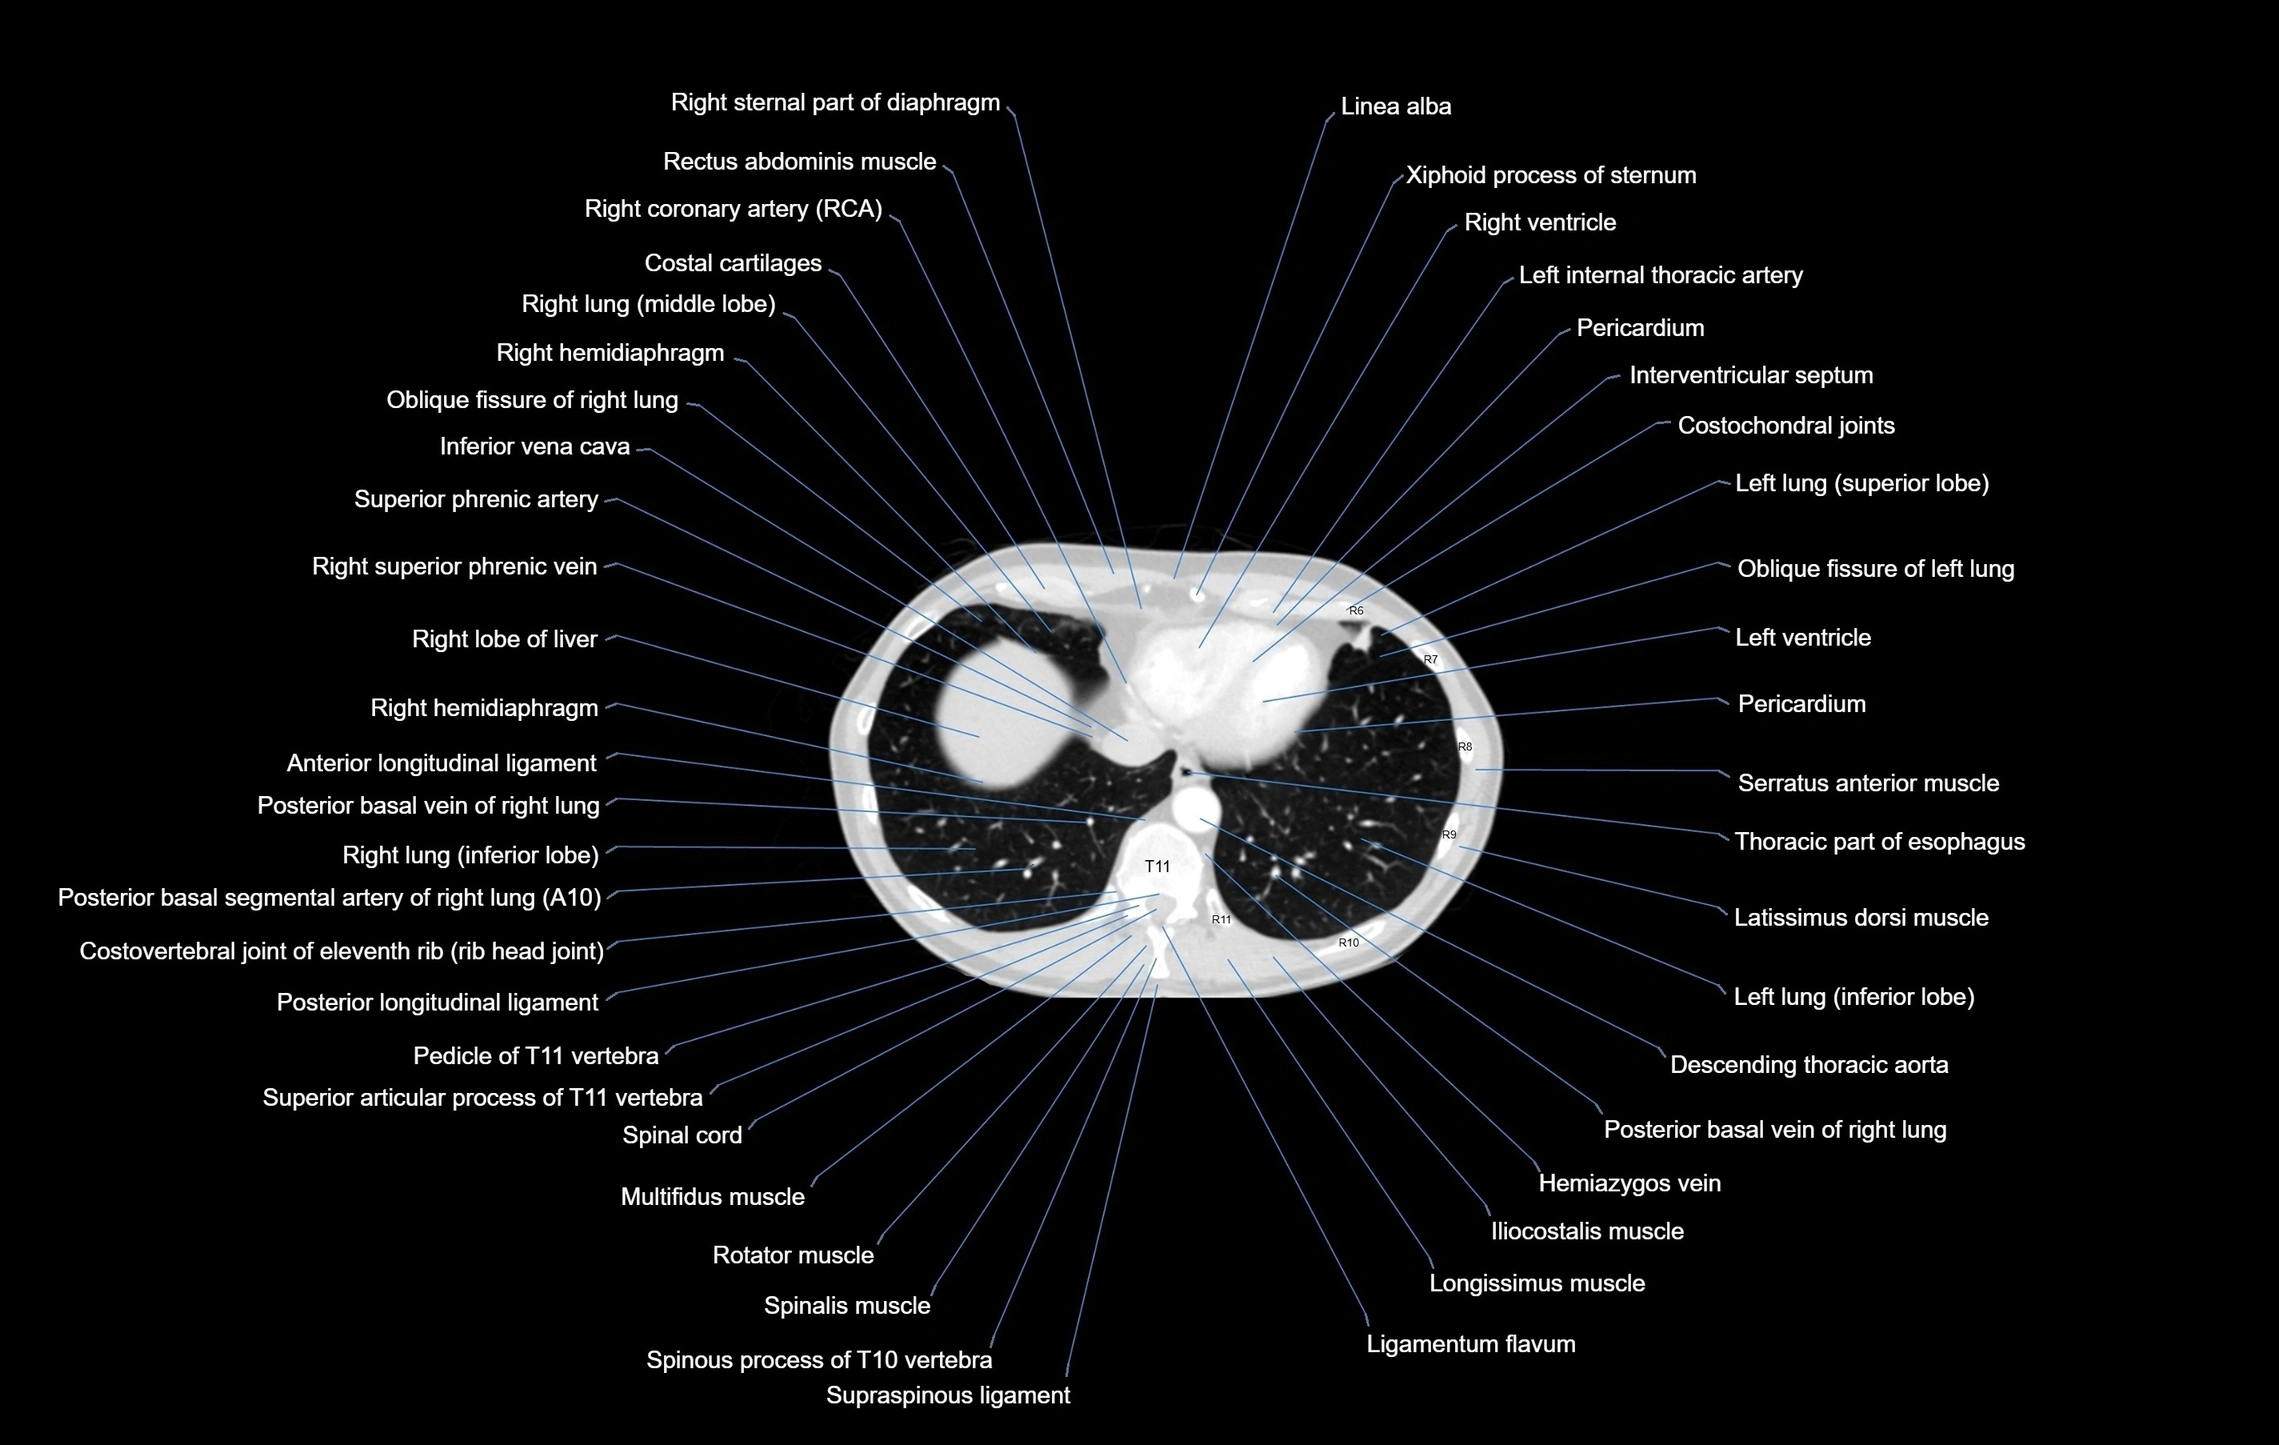

CT images